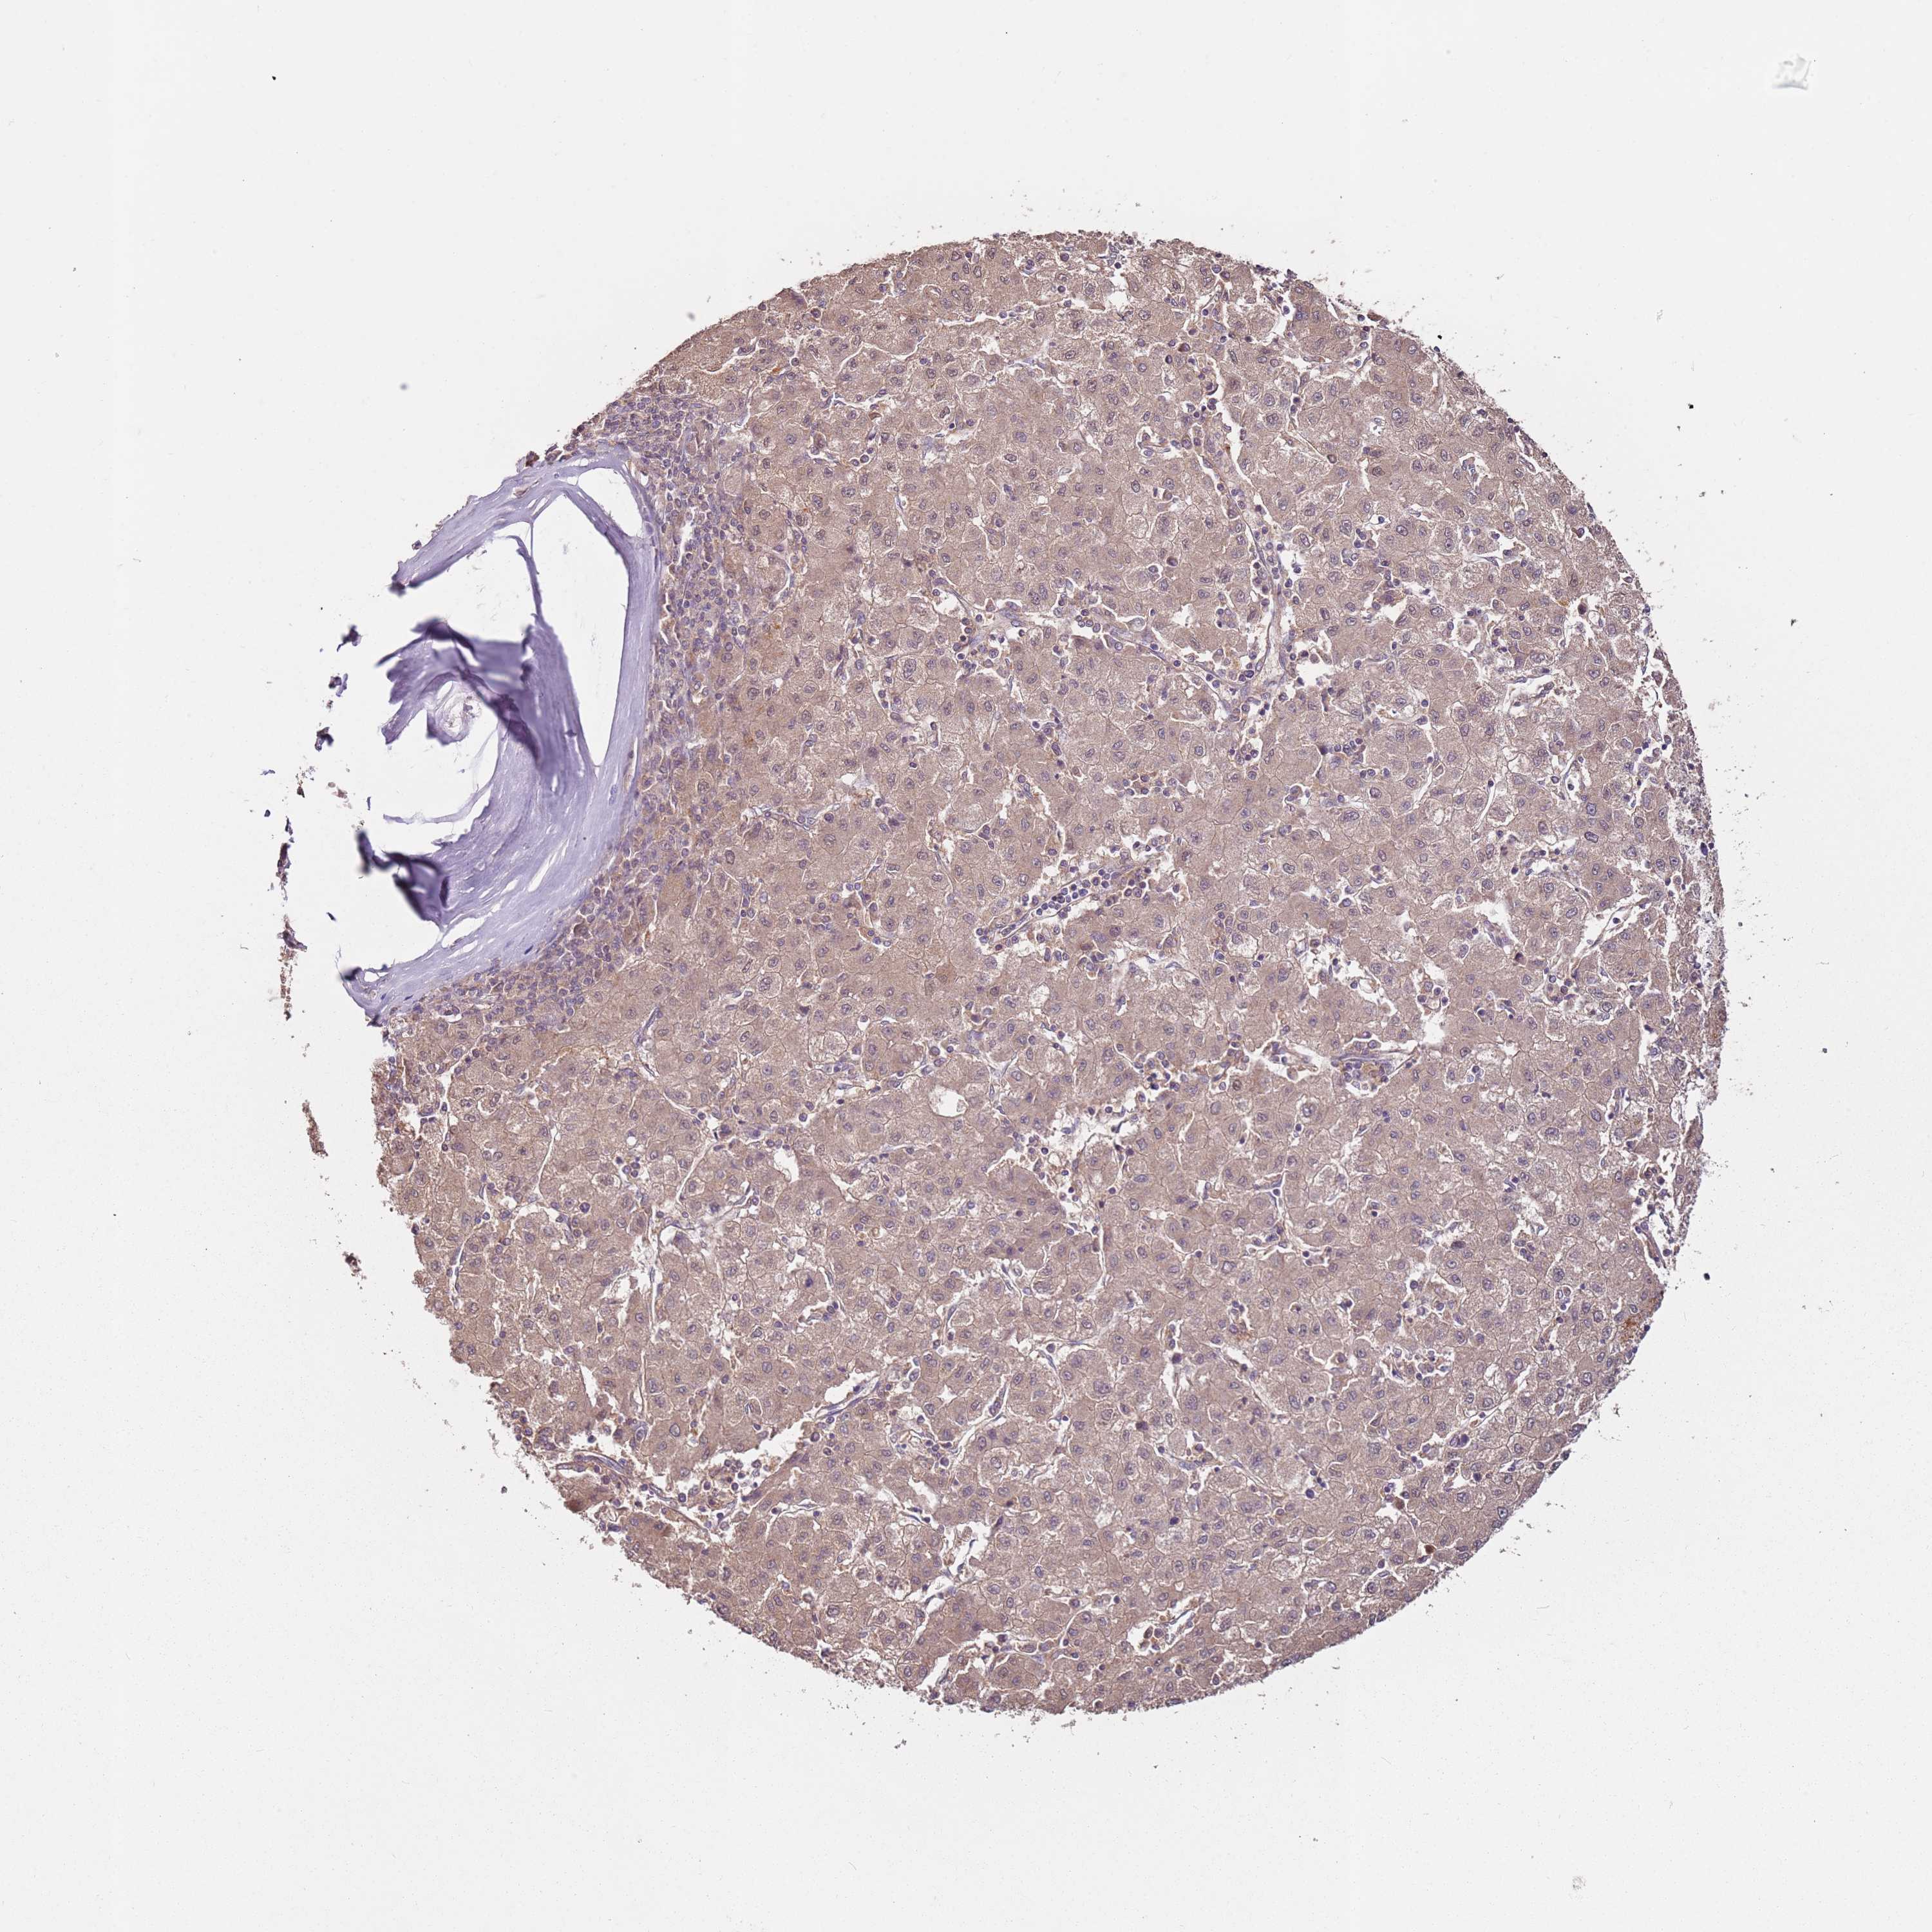

LIVER CANCER - Protein expressioni

A mouse-over function shows sample information and annotation data. Click on an image to view it in a full screen mode. Samples can be filtered based on level of antibody staining by selecting one or several of the following categories: high, medium, low and not detected. The assay and annotation is described here.

Note that samples used for immunohistochemistry by the Human Protein Atlas do not correspond to samples in the TCGA dataset.

Antibody stainingi

Antibody staining in the annotated cell types in the current human tissue is reported as not detected, low, medium, or high, based on conventional immunohistochemistry profiling in selected tissues. This score is based on the combination of the staining intensity and fraction of stained cells.

Each image is clickable and will lead to virtual microscopy that enables deeper exploration of all samples and also displays staining intensity scores, fraction scores and subcellular localization as well as patient and tissue information for each sample.

Antibody HPA027296

Antibody HPA054276

Antibody CAB047333

Staining

High

Medium

Low

Not detected

Intensity

Strong

Moderate

Weak

Negative

Quantity

>75%

75%-25%

<25%

None

Location

Nuclear

Cytoplasmic/membranous

Cytoplasmic/membranous,nuclear

Cholangiocarcinoma

Carcinoma, Hepatocellular, NOS